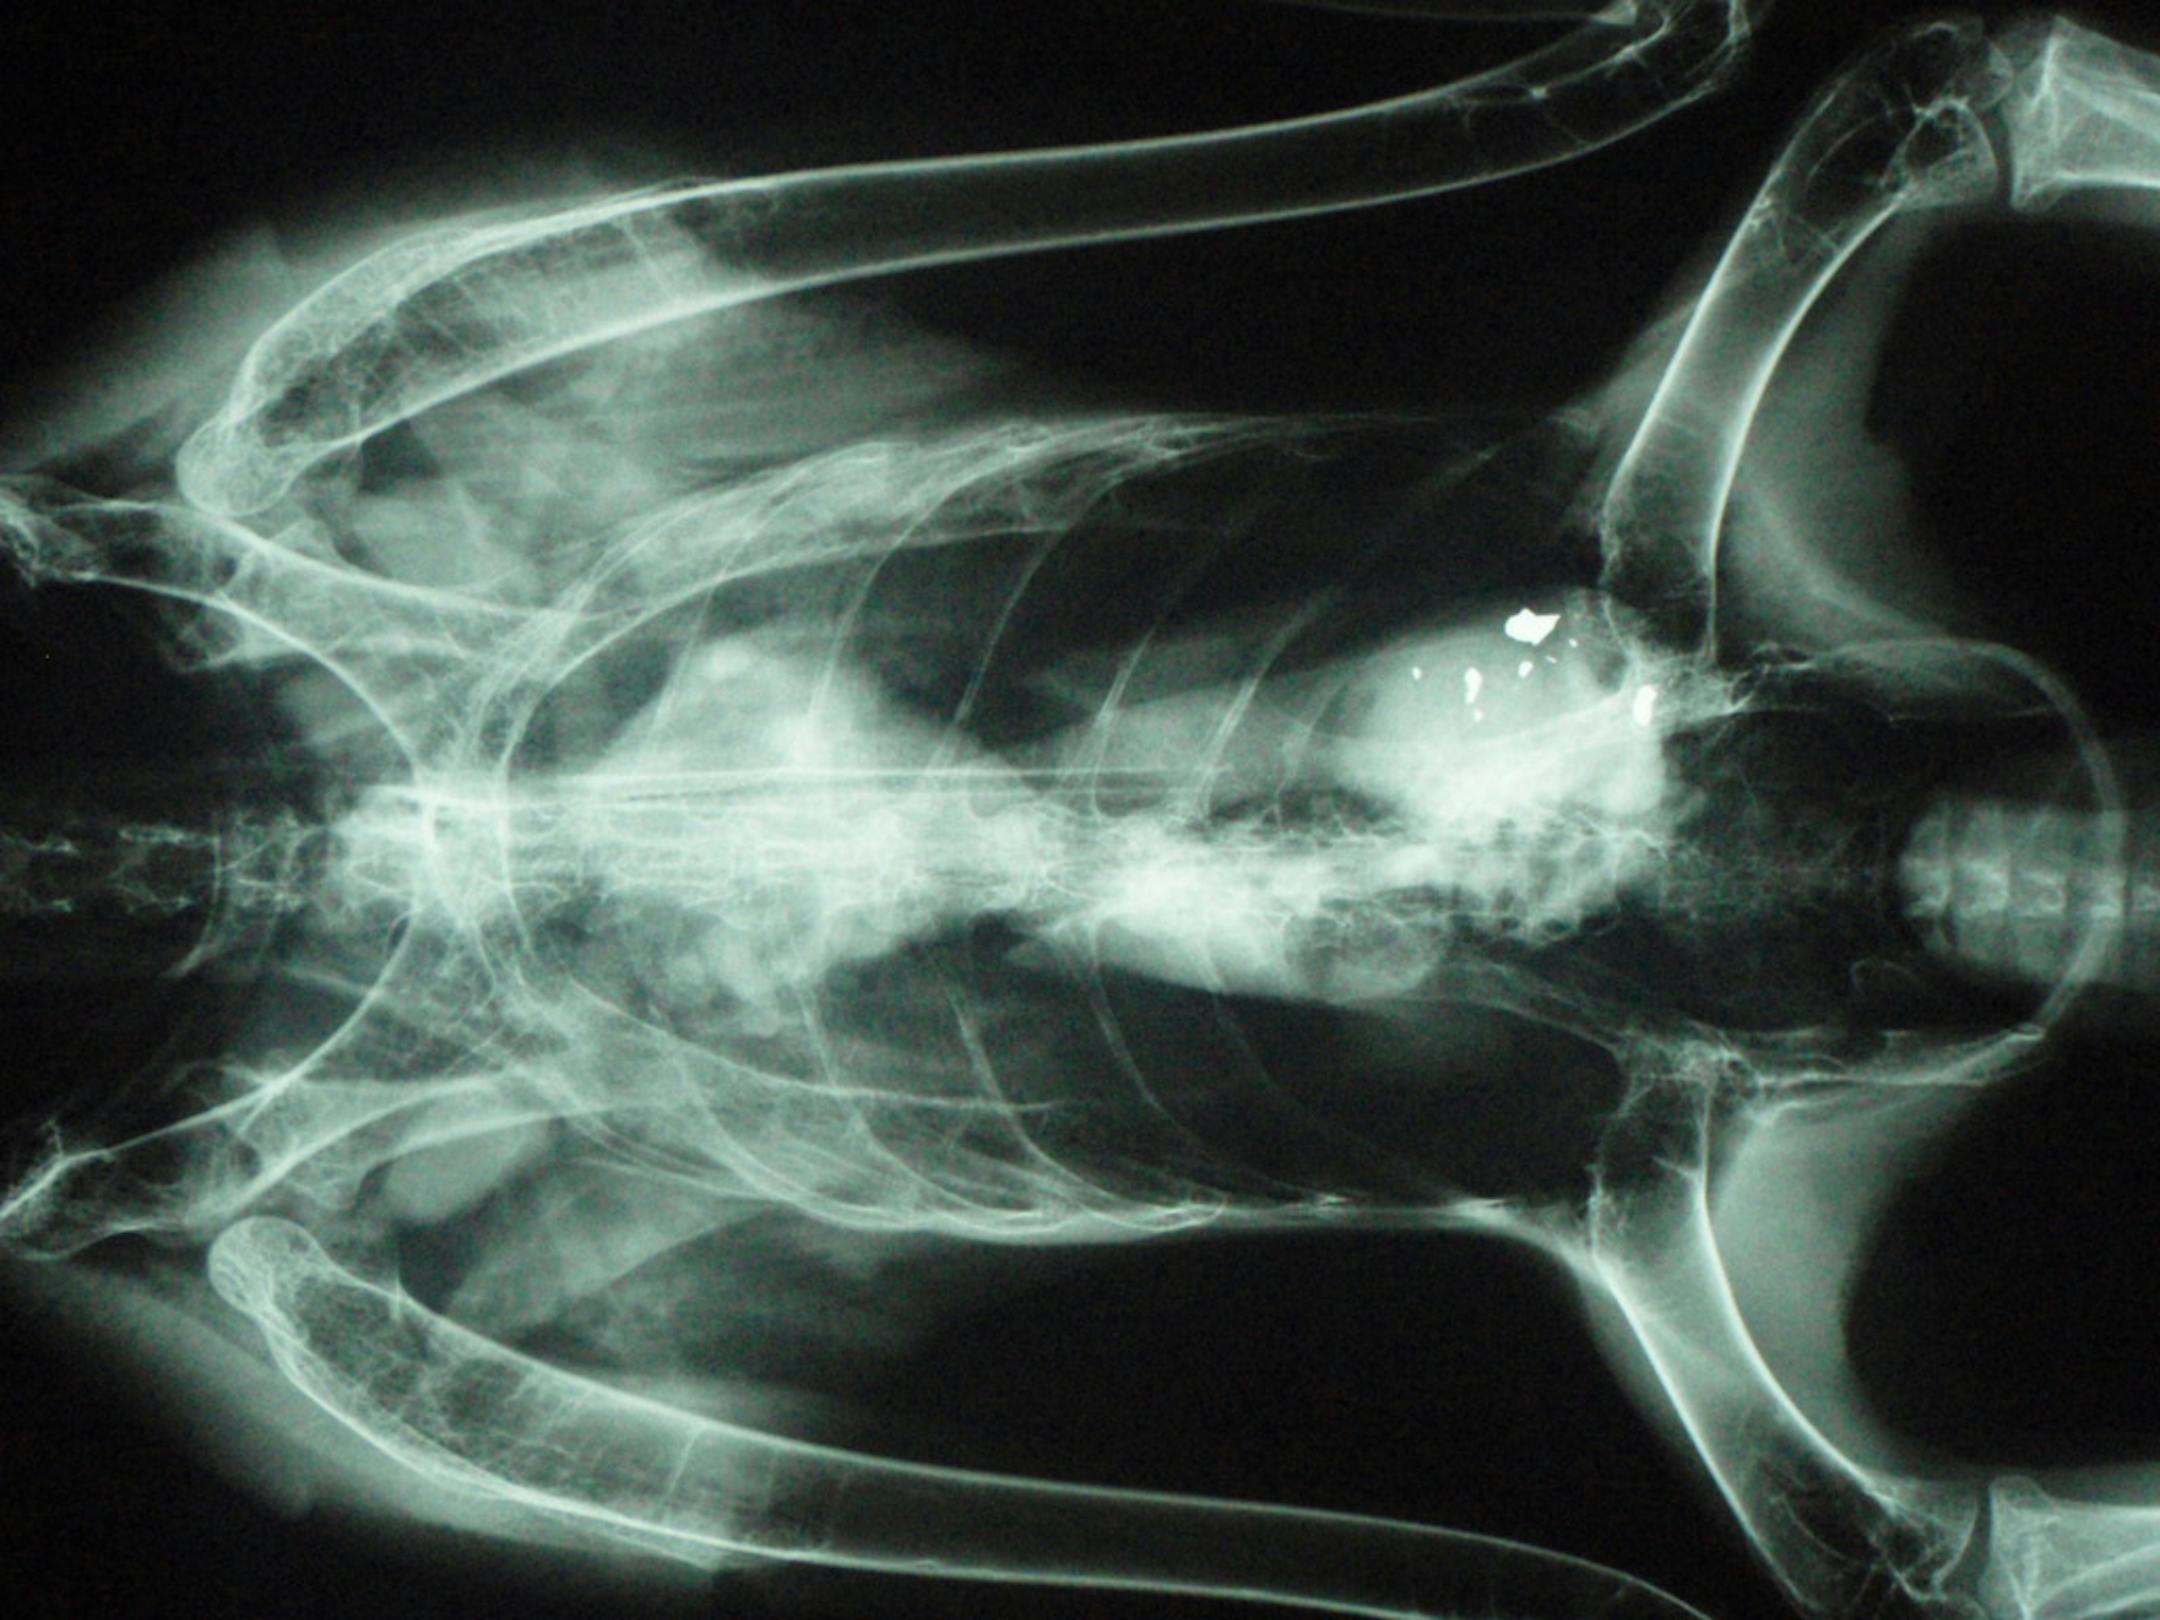

Lead bullet fragments are visible in the gastrointestinal tract of an eagle in this X-ray taken by Dr. Luis Cruz-Martinez. He said there is strong evidence that Minnesota eagles are being poisoned by eating lead bullet fragments left in deer carcasses.

Lead bullet fragments are visible in the gastrointestinal tract of an eagle in this X-ray taken by Dr. Luis Cruz-Martinez. He said there is strong evidence that Minnesota eagles are being poisoned by eating lead bullet fragments left in deer carcasses. (Star Tribune/The Minnesota Star Tribune)